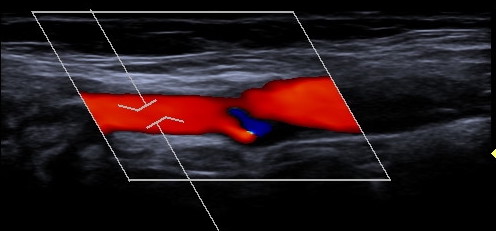

Gefäßdarstellung mittels Ultraschall

Bei der Doppler-Duplex-Sonographie der Halsgefäße wird untersucht, ob Verkalkungen (Plaques) vorliegen, und ob es dadurch zu Verengungen (Stenosen) kommt.

Neben dem Aussehen der Plaques wird die lokale Flussgeschwindigkeit des Blutes beurteilt: Je schneller die Flussgeschwindigkeit, desto hochgradiger die Stenose.

Bei Vorliegen einer Stenose ist bei geringem Schweregrad häufig eine Verlaufskontrolle bzw. ein Cholesterin-senkendes Medikament ausreichend.

Hochgradige Stenosen können eine Gefäßoperation erforderlich machen.